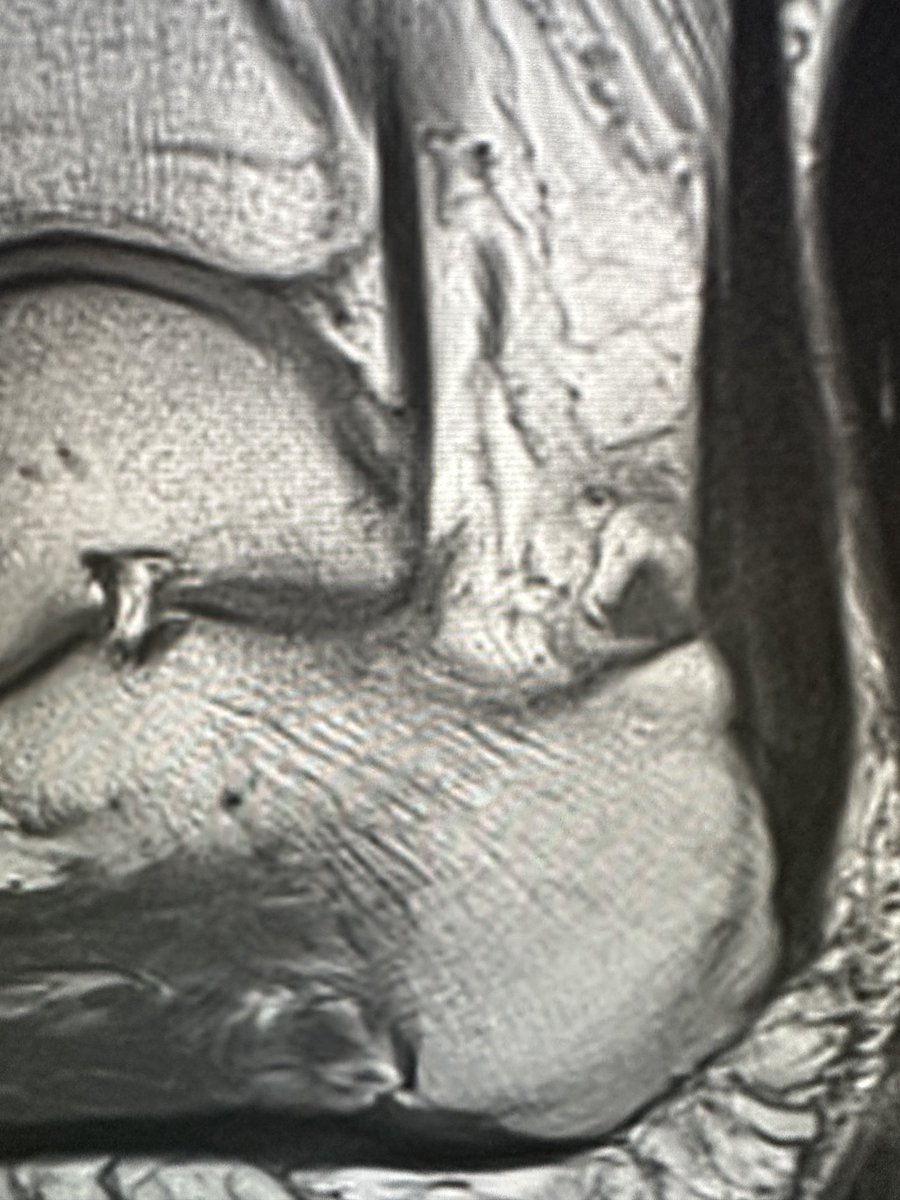

MRI VIBE sequences ('pseudo CT') are excellent for detailed assessment of pars stress injuries

This can be repeated to assess pars bony healing which takes longer than other BSIs (~3-6 months)

James Noake@DrJN_SportsMed

another adolescent case! 16yo high level MMA & jiu jitsu. Extension related LBP & esp pivoting /kicking. MRI great for picking up bone oedema across pars - the MRI VIBE sequences are CT like - 👍for further bony detail. This boy has bilateral pars defects / stress response 😞